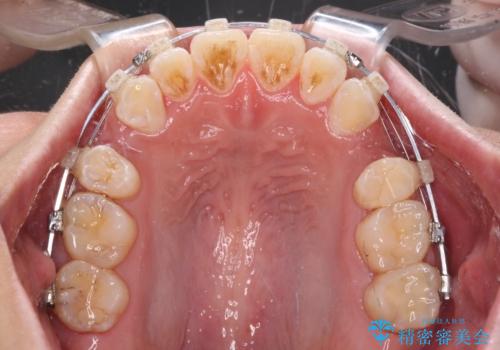

- クリアブラケット

- 前歯のクロスバイトと、口元が閉じにくいとのことで来院された患者様です。

口元の突出感を改善する必要があるため、上下左右の第1小臼歯4本を抜歯し、ワイヤー装置にて矯正治療を行うこととしました。

むし歯のリスクが高かったため、治療が長期化しないように心がけました。

当初の予定通り、2年強で無事に治療を終えることができました。